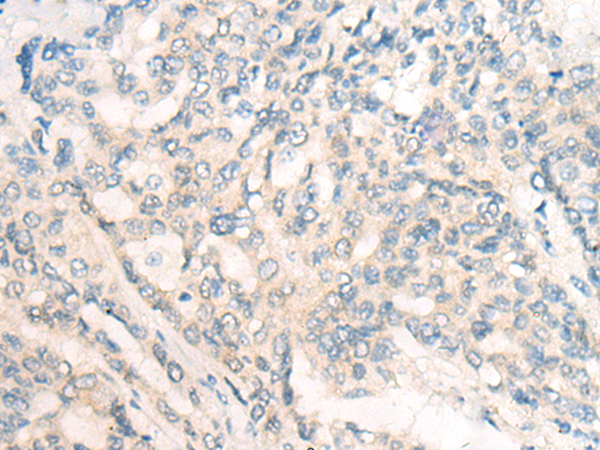

分类: 科研抗体货号: P10762别名: MDL1; MDL-1; CLECSF5应用: IHC反应种属: Human